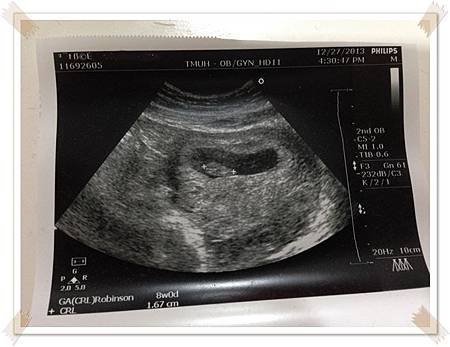

5W後醫生和我約8W回診照心跳

8W順利照到心跳了此時寶寶的大小都是用全長來測量